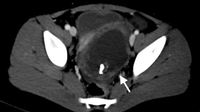

Tomografia computadorizada (TC) de menina revelando torção ovariana. Grande lesão cística pélvica com calcificações (seta branca) consistentes com teratoma ou cisto dermoide